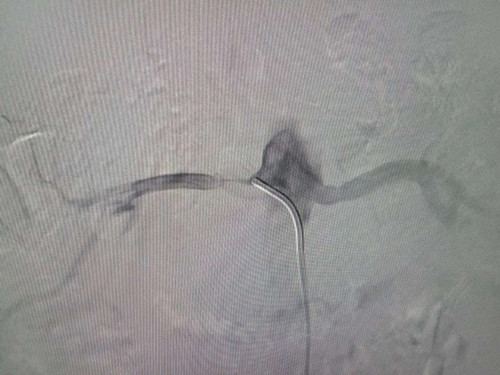

近日,我院内分泌科收治了一名年轻患者,28岁,男性,血糖升高6年,头晕伴左手麻木3天。经过完善的相关检查,诊断为:2型糖尿病、糖尿病酮症、糖尿病肾病、急性脑梗死、高血压3级很高危。在给予有效降糖、降压、营养脑细胞等治疗下,内分泌科联合介入中心对患者进行全脑血管造影及肾动脉造影,造影显示右侧肾动脉重度狭窄(狭窄率80%),左侧椎动脉重度狭窄(狭窄率80%),经过进一步仔细检查,分析病情,最终考虑患者多年的高血压病为肾动脉狭窄所致,决定对患者进行肾动脉支架置入术及球囊扩张术,手术于06-14上午9点开始,经过1.5小时治疗,支架顺利植入右侧肾动脉,左侧肾动脉成功进行球囊扩张,双侧肾动脉血流明显改善,术后患者血压下降并维持正常。患者年龄较小,但是多年的糖尿病及高血压病导致大血管病变较重,经过此次介入精准治疗,使患者的高血压病得以缓解,明显降低了靶器官损害的风险。